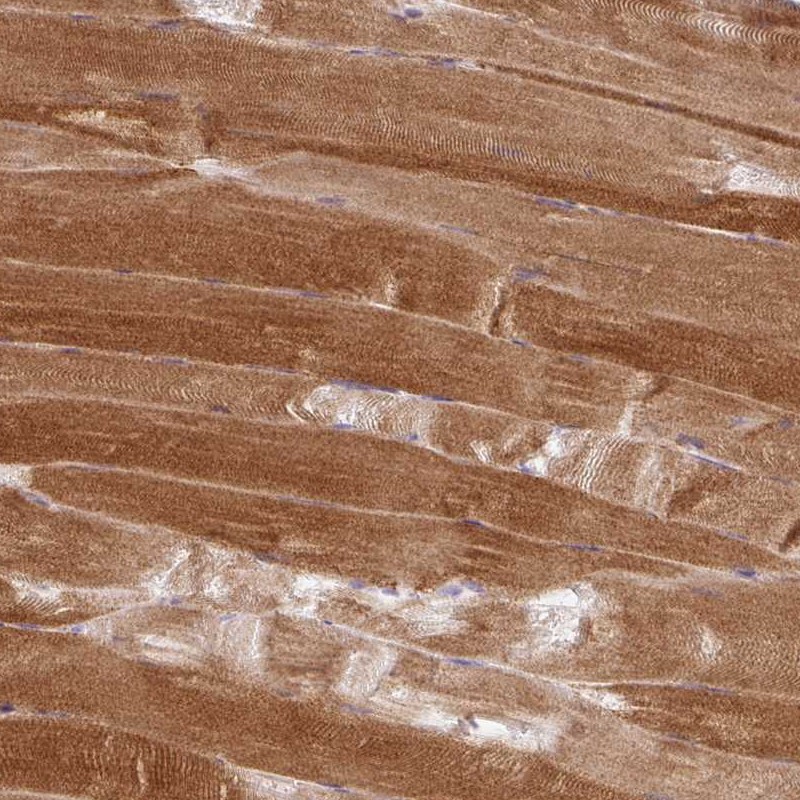

Immunohistochemical staining of human skeletal muscle shows strong cytoplasmic positivity in myocytes.